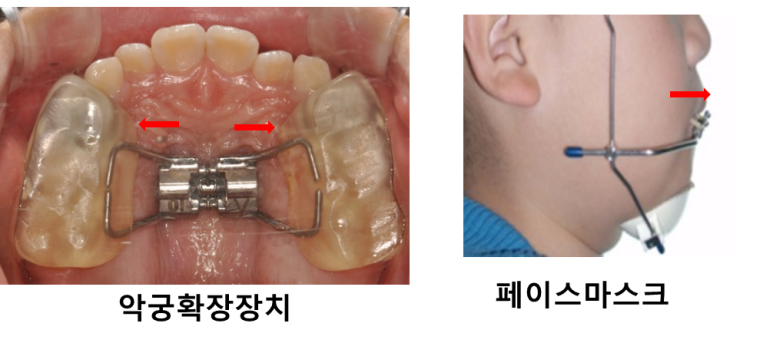

악궁확장장치와 페이스마스크 장치를 이용하여

위 턱을 넓히고 위 턱을 앞으로 끌어내 주며

아래턱이 나오는 힘을 위 아래로 분산시켜 줍니다.